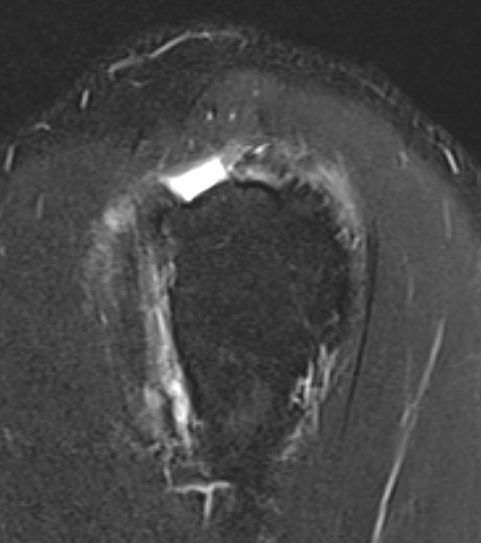

Goutallier classification

Amount of fatty degeneration in rotator cuff muscle belly on a T1 sagittal MRI

- systematic review of Goutallier grade and retear rates

- retear rates after surgical repair increase as the Goutallier stage increases

Stage 0: normal muscle

| Stage 3 | Stage 4 |

|---|---|

|

Equal fat and muscle MRI demonstrates grade 3 supraspinatus and infraspinatus |

More fat than muscle MRI demonstrates grade 4 infraspinatus |